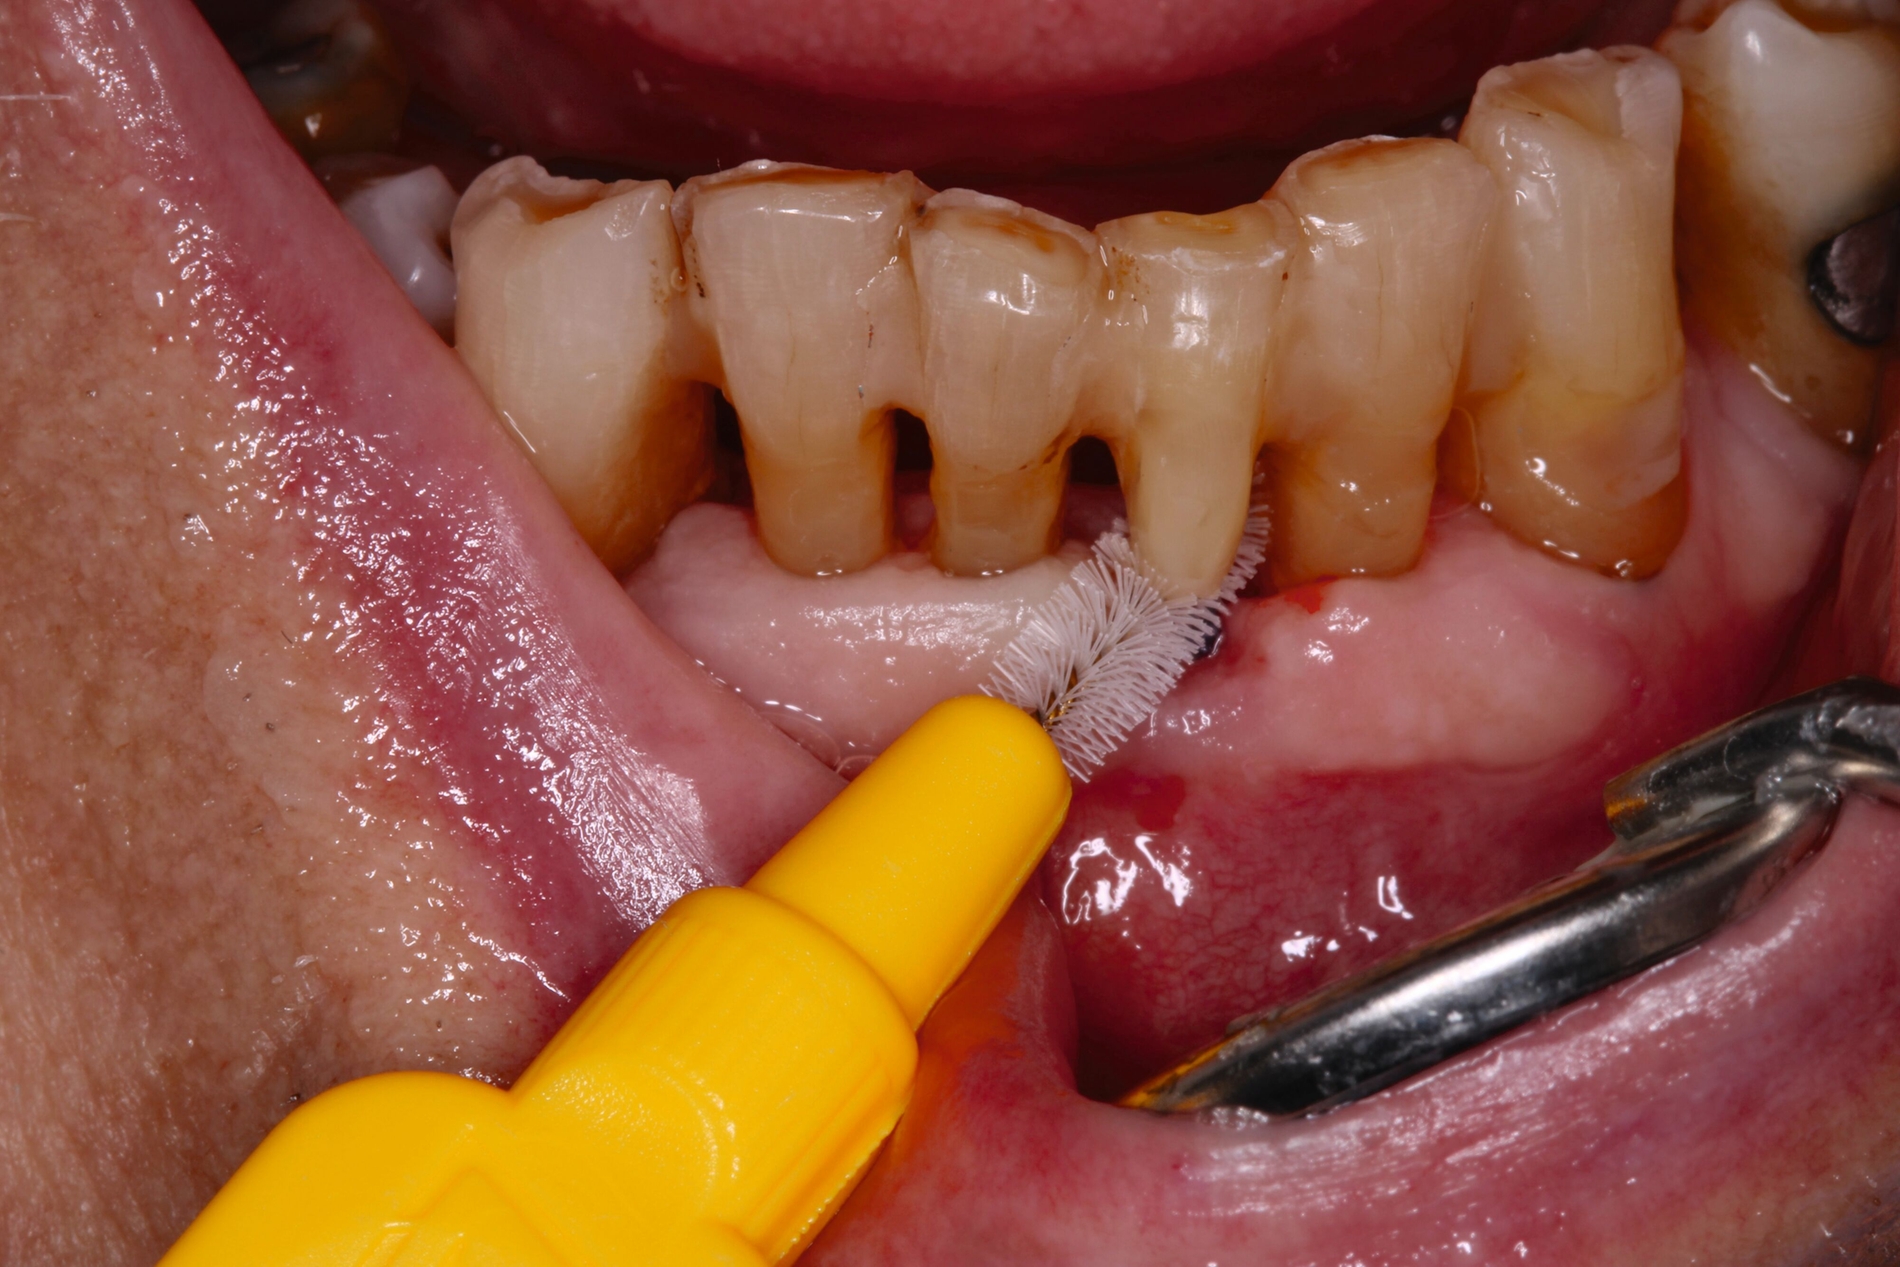

Auch aufseiten der Pflege wurden durch die Einführung des DNQP-Expertenstandards Rahmenbedingungen zur Verbesserung der Mundgesundheit bei Personen mit Pflegebedarf geschaffen. Der Expertenstandard definiert unter anderem das Aufgabenspektrum, den Verantwortungsbereich und das nötige Kompetenzprofil von Pflegefachpersonen in Bezug auf die Mundgesundheit bei Personen mit Pflegebedarf. Als zentrale Anforderung an Pflegefachpersonen formuliert der Expertenstandard zudem die Kompetenz, einschätzen zu können, wann weitere zahnmedizinische Expertise hinzuzuziehen ist [Sirsch et al., 2022]. Um die Maßnahmen zur Förderung der Mundgesundheit nachhaltig zu implementieren, ist ein dauerhafter Austausch zwischen Zahnmedizinern und Pflegeverantwortlichen, unter regelmäßiger Einbeziehung geriatrisch-hausärztlicher Expertise notwendig. Die Telemedizin verspricht in Bezug auf die Verbesserung des Zugangs zu zahnmedizinischen Leistungen für Personen in Pflegeeinrichtungen Zukunftspotenzial [Aquilanti et al., 2020]. Nicht in allen Fällen sind Defizite der Mundhygienefähigkeit absehbar. Nach Unfällen oder Schlaganfällen sind Patientinnen und Patienten eventuell von einem auf den anderen Tag nicht mehr in der Lage, ihre Mundhygiene selbstständig adäquat durchzuführen (Abbildung 4).